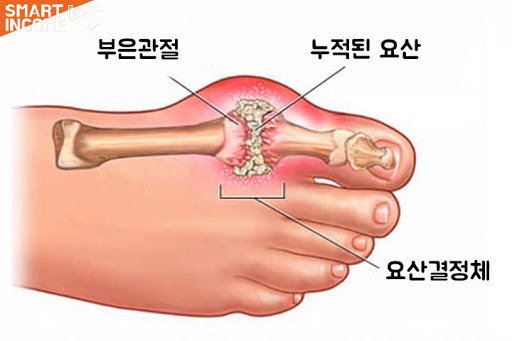

통풍 환자에서는 혈액 내 요산이 지나치게 많아서 이것이 결정체로 변하고,

이 요산 결정체가 관절 내에 침착하여 염증을 유발하게 되는 것입니다.

통풍성 결절이라 불리는 덩어리가 관절 주위나 피하조직에 나타나기도 하며,

1) 주로 엄지발가락, 발목, 무릎 등 한군데 관절이 갑자기 빨갛게 부어오르고